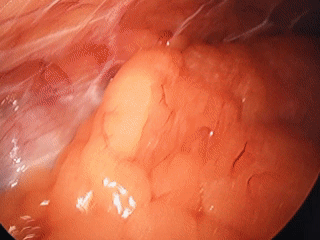

主刀医师凭借丰富的经验和沉稳的手法,在“蜘蛛网”般的间隙中谨慎探索。利用腹腔镜的角度优势,她逐一避开与腹壁粘连的肠管等器官,对遮挡视野的粘连组织进行精细松解。在清晰显露胆囊三角后,手术团队一气呵成,成功将胆囊完整切除并装入标本袋取出。

术中出血量少。这场原本极大概率需要“开大刀”的手术,最终以仅有的几个微小戳孔宣告成功。